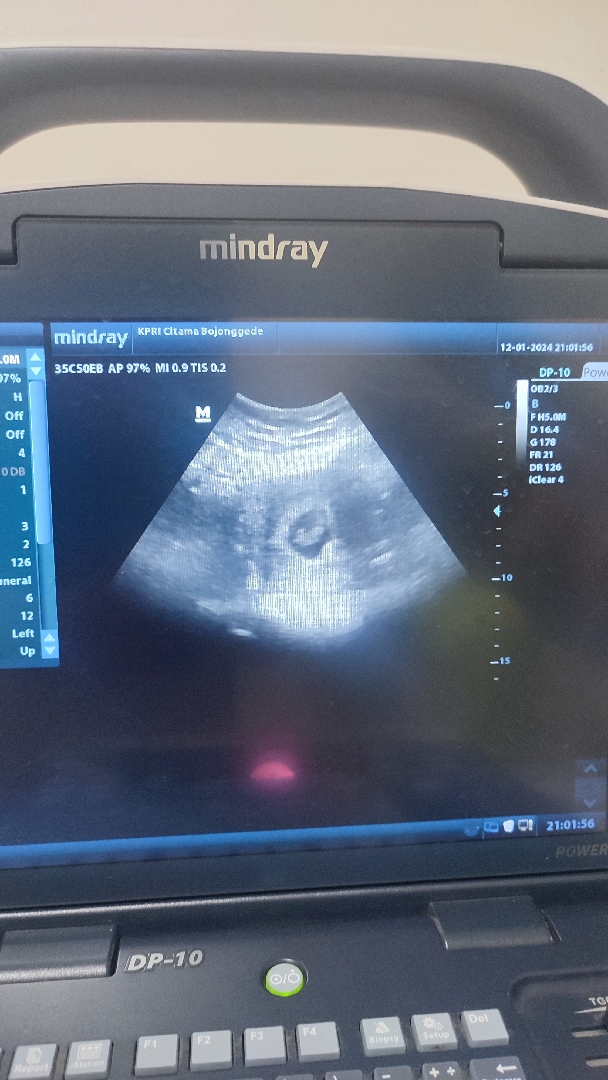

Bund, saya belum USG, tapi kemarin abis kontrol sm bidan cek kaya gini. Ini sama aja kaya USG bukan si bund ๐คฃ Udsh kelitan kantung dedenya ya. Maklum bund new mum ini

Itu usg yg protable bun, bisa dibawa kemana2. Sama aja kok bun. Cmn lebih burem aja..๐ selamat bunda, sehat sehat yaaa.๐ฅฐ

Iya itu usg namanya bunda, cuma memang klo dibidan biasanya tampilannya ga sejernih di SpOG , dan layarnya kecil